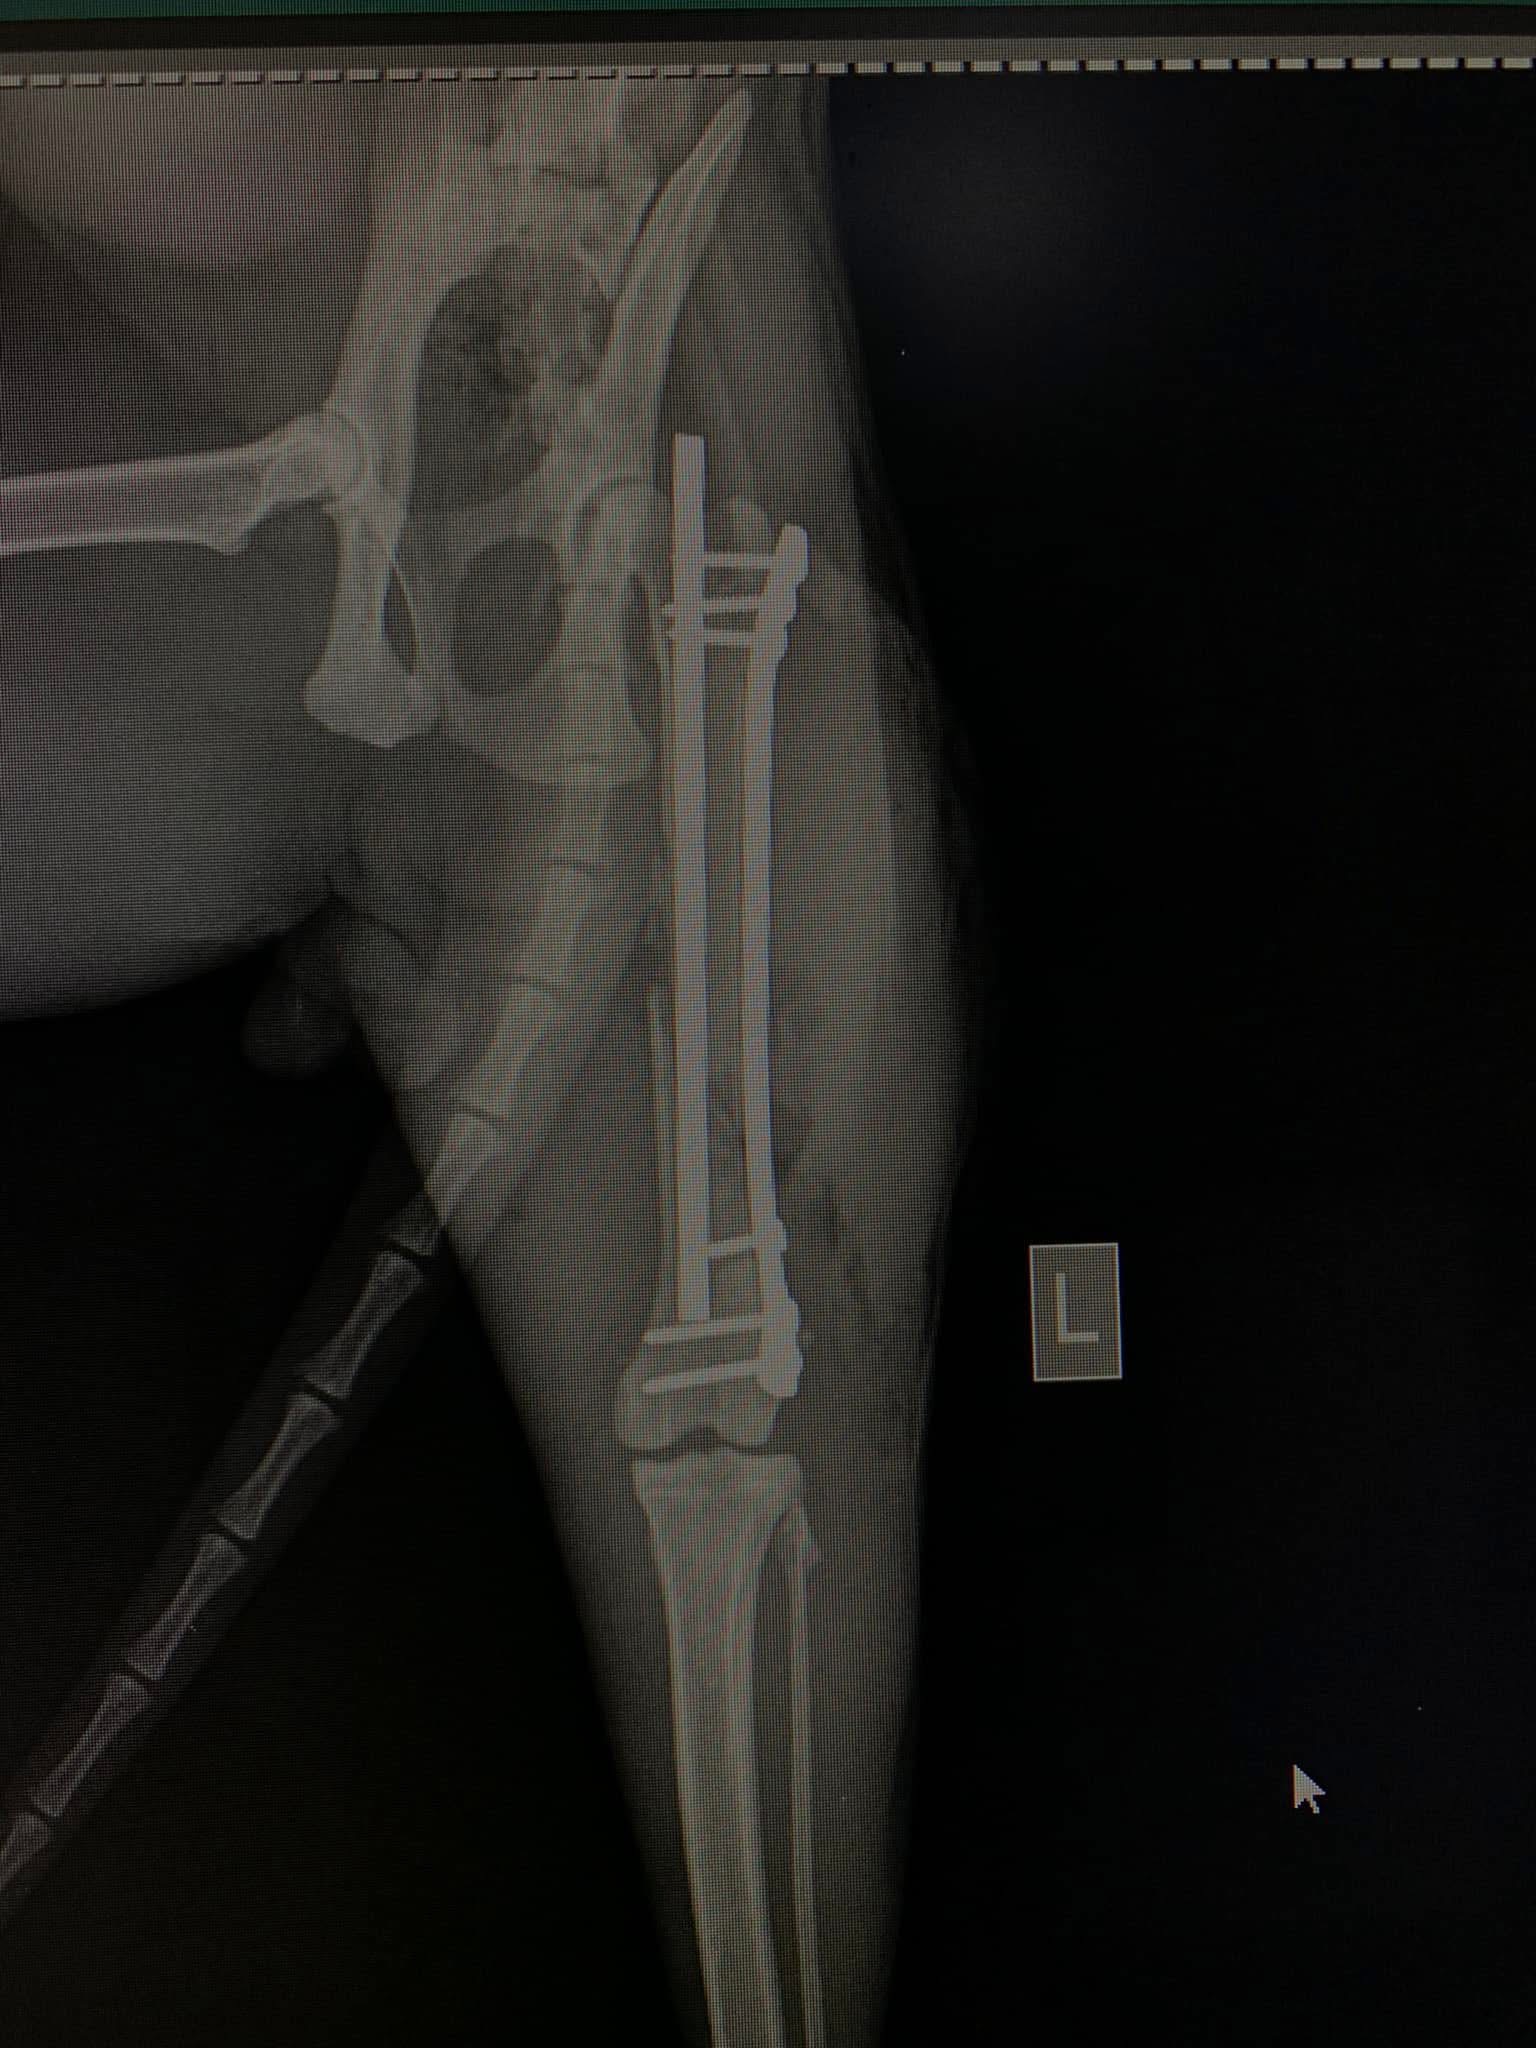

- Liječenje prijeloma kostiju, uključujući intraartikularne frakture

- Liječenje rupture prednjeg križnog ligamenta koljena TPLO (eng. Tibial Plateau Leveling Osteotomy)